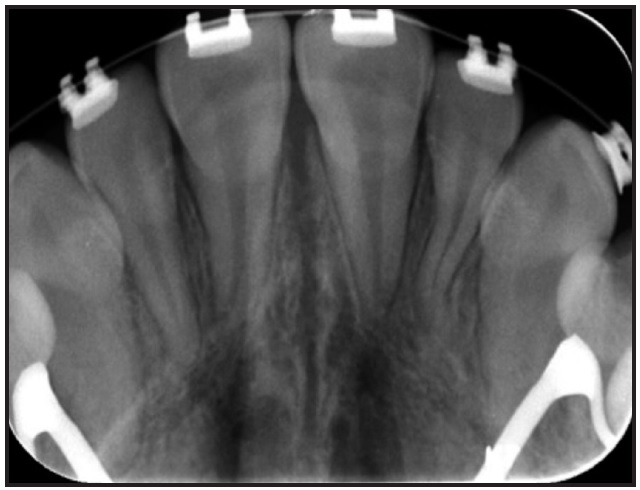

Fig. 5 Case 1. Occlusal radiograph indicating mild sutural disruption after expansion.

After intermolar expansion of 3.87mm had been obtained (Fig. 3, Table 1), flowable composite was placed in the expansion screw housing to stabilize the appliance. A maxillary impression was then obtained and digitized to evaluate the molar angulation changes (Fig. 4). Bony separation suggesting mild sutural disruption was indicated by radiolucency on the occlusal radiograph (Fig. 5).